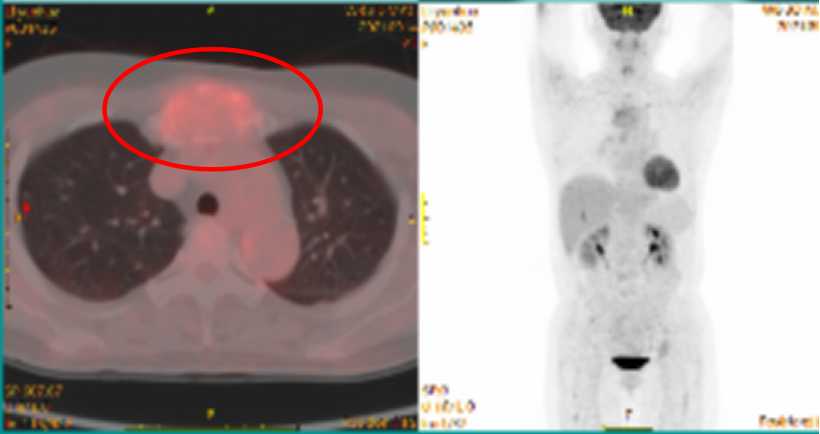

PET-CT:胸骨,右侧肩胛骨,脊柱多个椎体及部分附件,双侧多条肋骨,双侧髂骨,左侧耻骨多发溶骨性骨质破坏,伴软组织形成,部分FDG摄取不同程度增高,SUVmax为6.0,考虑多发性骨髓瘤可能。

640 (1).png

PET-CT检查情况

PET-CT检查(6疗程治疗前 vs 治疗后):原胸骨,右前第3肋骨,右侧肩胛骨,T2、4,L4、5椎体,T4、6附件,双侧第11后肋,双侧髂骨,左侧耻骨多发溶骨性骨质破坏伴FDG代谢不同程度增高,SUVmax为6.0;本次骨质破坏灶周边可见硬化边,部分骨质破坏灶内可见高密度影,FDG代谢程度部分较前增高,部分较前减低,SUVmax为7.4;原骨质破坏灶周围FDG代谢增高软组织密度影,本次显像未见明显FDG代谢增高。

640 (3).png

PET-CT检查情况(左:6疗程治疗前,右:6疗程治疗后)